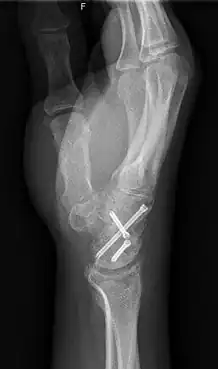

ScaphoidectomyWCarpalFusion 2 L

X-ray of a wrist that has undergone carpal arthrodesis (fusion of the wrist joint). In this case, this means that screws have been inserted through multiple wrist bones so they are now immobilized. Over time, these bones will fuse together, preventing them from rubbing against each other and causing pain.

Arthrodesis is the surgical immobilization of bones within a joint to promote fusion of the joint.[5] Arthrodesis is performed most commonly on joints of the feet, hands, and spine.[6][7][8] Arthrodesis can relieve pain from arthritis and fractures.[9] This is accomplished through the use of orthobiologics such as allografts and autografts.[10] Allografts are done by creating bone grafts from a donor bone bank, whereas autografts are bone grafts from other bones in a patient's body.[10] Patient-reported outcomes following this procedure are typically positive in terms of long-term pain relief; however, the procedure also results in decreased range of motion.[11]